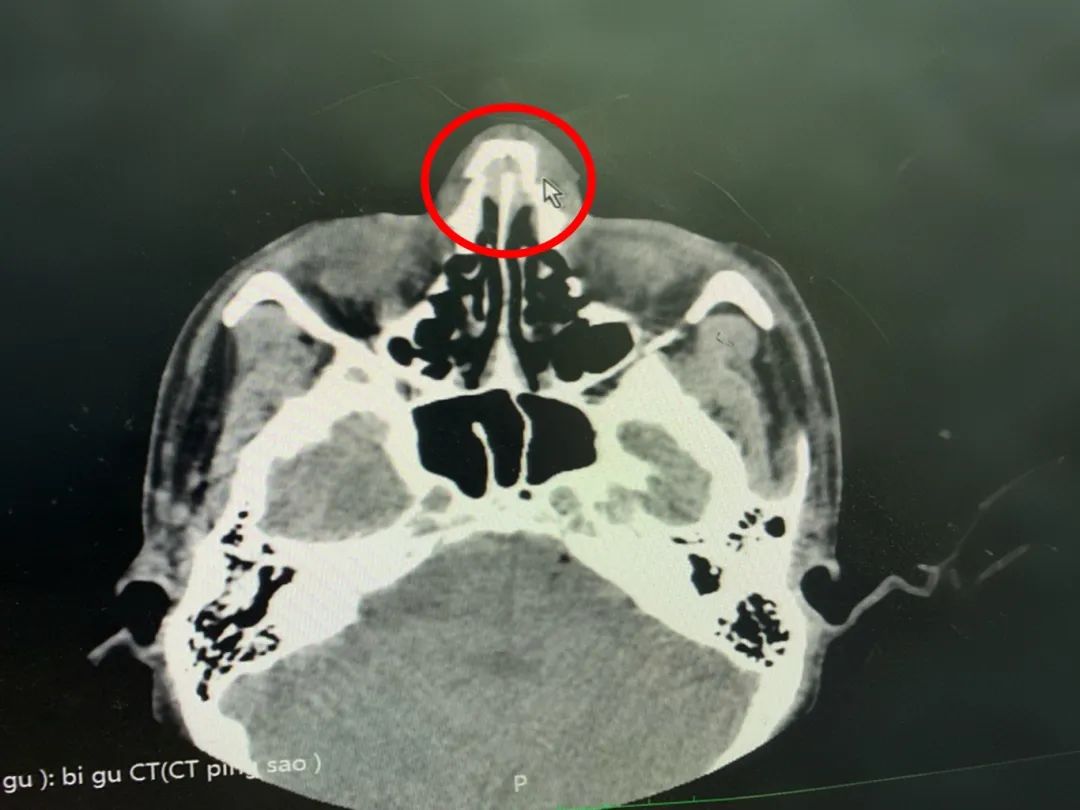

一位涉藏地區少年突發外傷,鼻部大量流鼻血,鼻周腫脹疼痛,外觀上歪鼻,并覺得頭部疼痛。經CT檢查顯示:雙側鼻骨骨折,斷端錯位,周圍軟組織稍腫脹。診斷:“鼻骨骨折”,當地醫院建議轉上級醫院就醫后,來到成都尋求專業的醫療服務。

鼻骨骨折的典型癥狀是鼻部疼痛、腫脹、外鼻變形、鼻出血、鼻塞等情況,當患者鼻部因撞擊、外傷等原因來院治療時,醫生會通過詳細的病史詢問、體查、CT、X光等影像學檢查準確判斷有無鼻骨折和骨折的位置、部位、類型、有無合并鄰近組織損傷,特別是鼻及顱面區復合骨折。明確診斷后,根據骨折的類型和位置,制定治療方案。